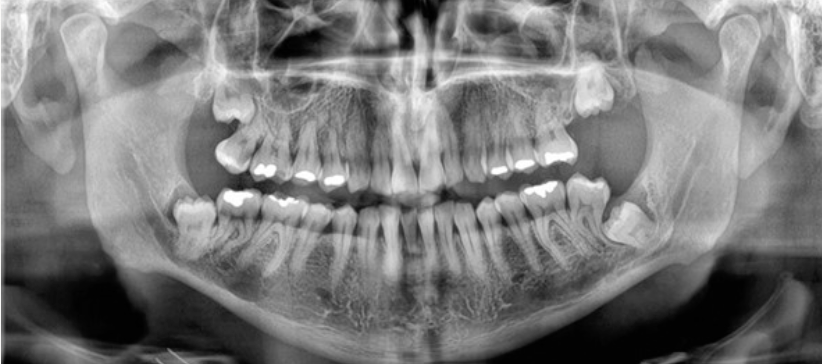

Panoramic radiograph showing deeply impacted wisdom teeth in close proximity to the mandibular nerve canals

The panoramic radiograph immediately raised the critical concern: both impacted wisdom teeth appeared to be in direct contact with the inferior alveolar nerve (IAN) canals. On a 2D panoramic, the relationship between an impacted tooth root and the nerve canal is often ambiguous — the structures overlap, and you cannot tell whether the root is buccal, lingual, or truly in contact with the canal. This is the exact scenario where extraction carries the highest risk of nerve injury.

Panoramic radiograph showing bilateral deeply impacted lower wisdom teeth with roots in apparent contact with the mandibular nerve canals

Fig. 1 Panoramic image clearly showing the deep impaction of both lower wisdom teeth (38 and 48) and their intimate relationship with the mandibular nerve canals. On this 2D view, it is impossible to determine the exact spatial relationship between the roots and the nerve.